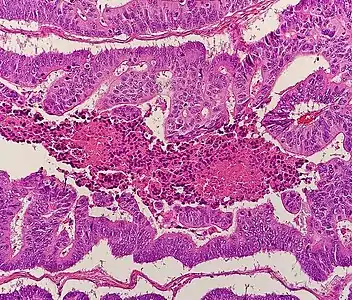

Histopathology

The histopathologic characteristics of the tumor are reported from the analysis of tissue taken from a biopsy or surgery. A pathology report contains a description of the microscopical characteristics of the tumor tissue, including both tumor cells and how the tumor invades into healthy tissues and finally if the tumor appears to be completely removed. The most common form of colon cancer is adenocarcinoma, constituting between 95%[69] to 98%[70] of all cases of colorectal cancer. Other, rarer types include lymphoma, adenosquamous and squamous cell carcinoma. Some subtypes have been found to be more aggressive.[71] Immunohistochemistry may be used in uncertain cases.